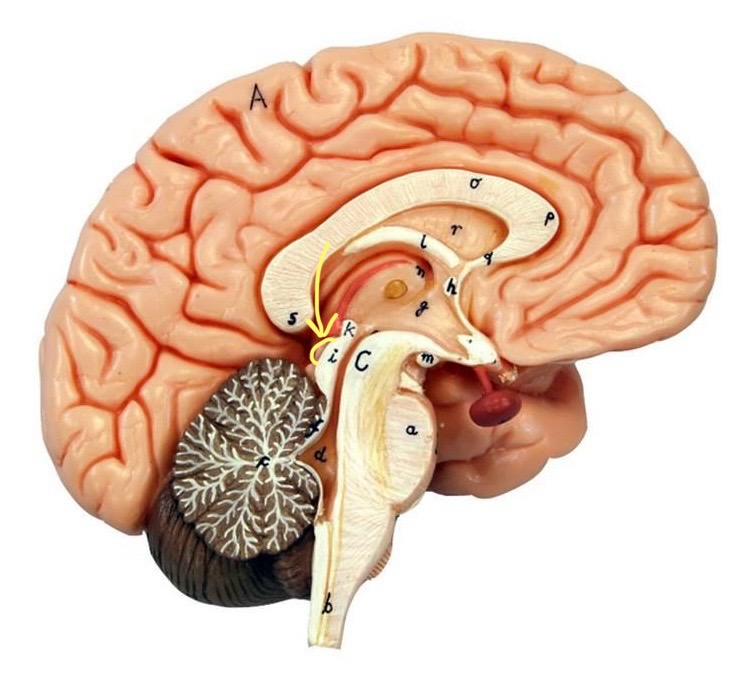

What is D?

lateral ventricle

Imagine thin membrane separating the 2 lateral ventricles

septum pellucidum

What is C?

3rd ventricle

What is B?

cerebral aqueduct

What is A?

4th ventricle

What is below A at the very end?

central canal (spinal cord)

What is C?

midbrain

tectum (corpora quadrigemina): superior colliculus

tectum (corpora quadrigemina): inferior colliculus

What is a?

pons

medulla oblongata

intermediate mass of thalamus

hypothalamus

What is the pink bulb?

pineal gland

corpus callosum

fornix

What is A?

cerebral cortex

cerebral tracts

cerebral hemispheres

longitudinal fissure

What are these ridges?

gyri

What are these shallow grooves?

sulci

Divides parietal from frontal lobe

central sulcus

precentral gyrus

postcentral gyrus